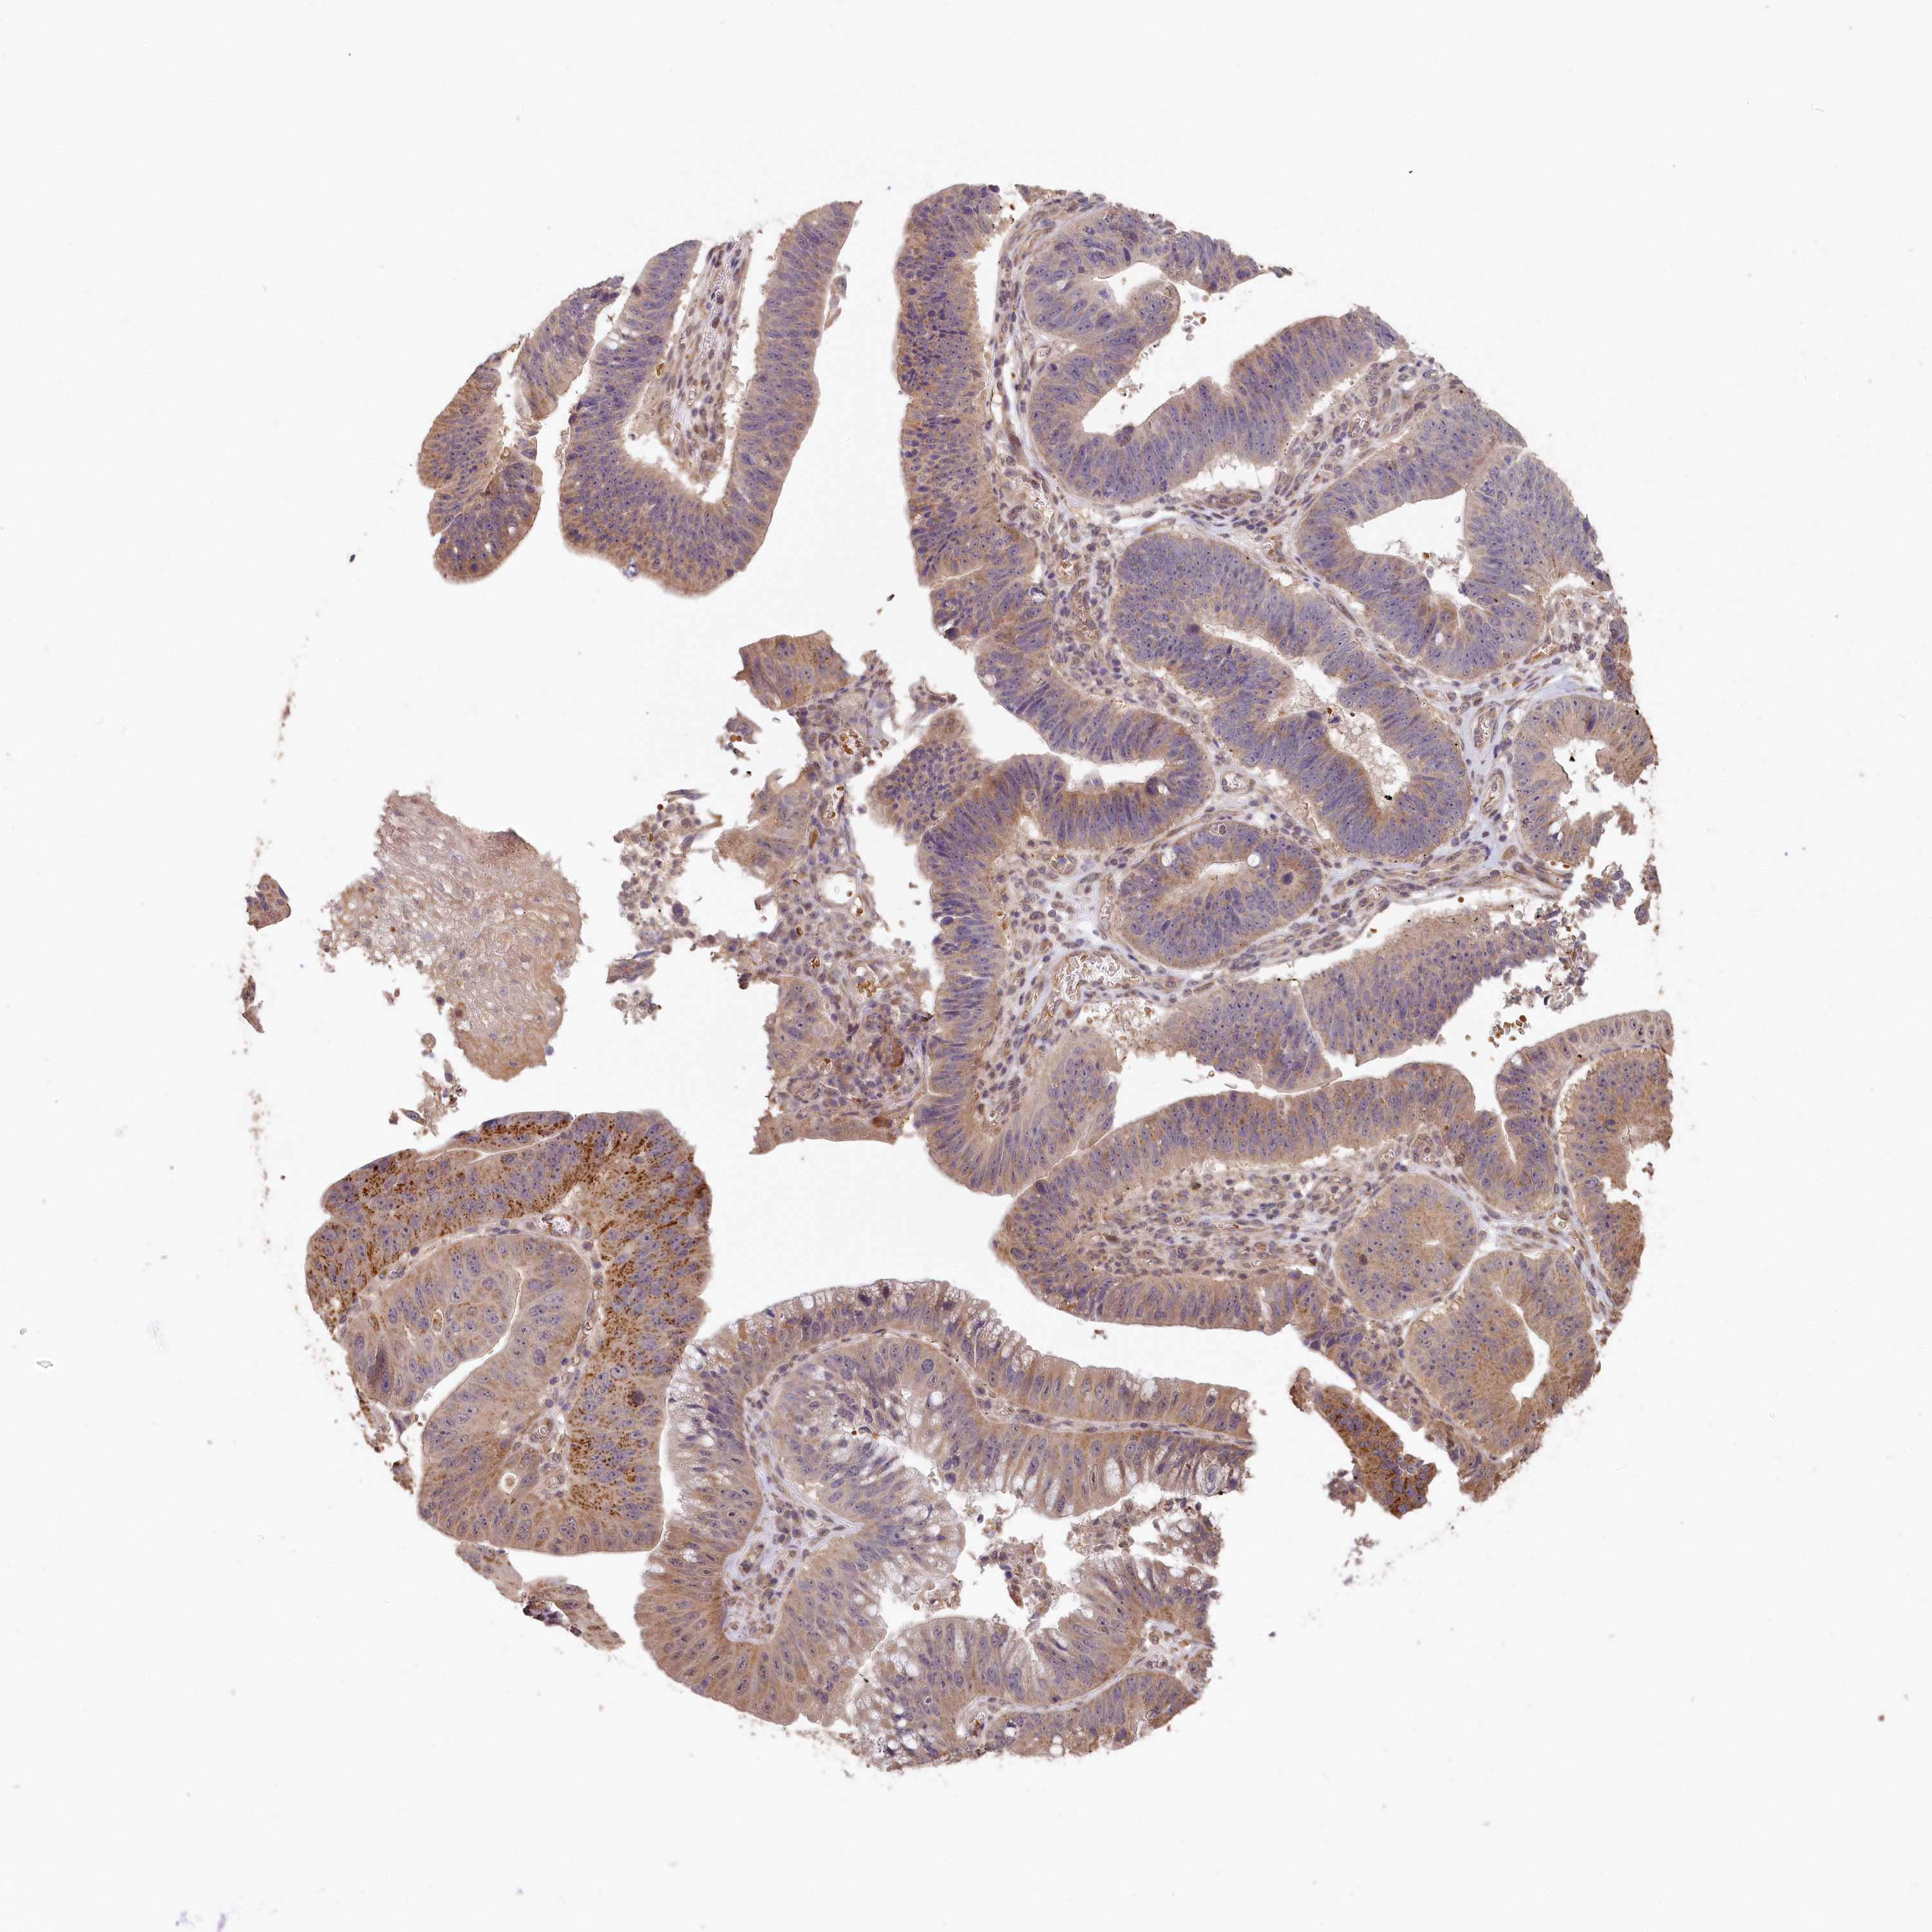

STOMACH CANCER - Protein expressioni

A mouse-over function shows sample information and annotation data. Click on an image to view it in a full screen mode. Samples can be filtered based on level of antibody staining by selecting one or several of the following categories: high, medium, low and not detected. The assay and annotation is described here.

Note that samples used for immunohistochemistry by the Human Protein Atlas do not correspond to samples in the TCGA dataset.

Antibody stainingi

Antibody staining in the annotated cell types in the current human tissue is reported as not detected, low, medium, or high, based on conventional immunohistochemistry profiling in selected tissues. This score is based on the combination of the staining intensity and fraction of stained cells.

Each image is clickable and will lead to virtual microscopy that enables deeper exploration of all samples and also displays staining intensity scores, fraction scores and subcellular localization as well as patient and tissue information for each sample.

Antibody HPA041019

Antibody HPA042033

Staining

High

Medium

Low

Not detected

Intensity

Strong

Moderate

Weak

Negative

Quantity

>75%

75%-25%

<25%

None

Location

Nuclear

Cytoplasmic/membranous

Cytoplasmic/membranous,nuclear

Adenocarcinoma, NOS